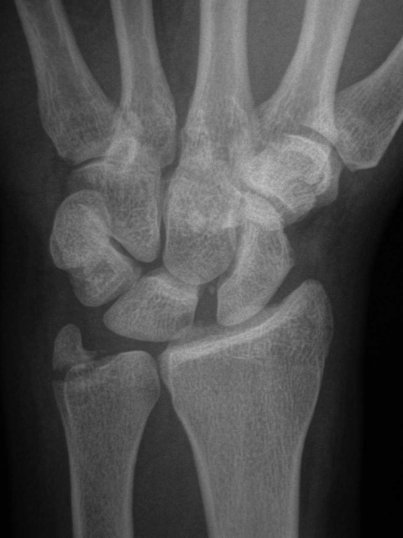

Radiographs

Radiographs reveal  key features of rotatory subluxation of the scaphoid.

Ap view

"Terry Thomas"sign gap between scaphoid and lunate normal 1-2 mm (abnormal 3mm)

Progressive flexion and foreshortening of the scaphoid leads to the scaphoid ring sign, seeing scaphoid end on.

Lateral view

Increased scapholunate angle normal 30-60º

Increased flexion of scaphoid and extension of lunate may progress to DISI (increase capitolunate angle >20º strongly suggestive of carpal instability